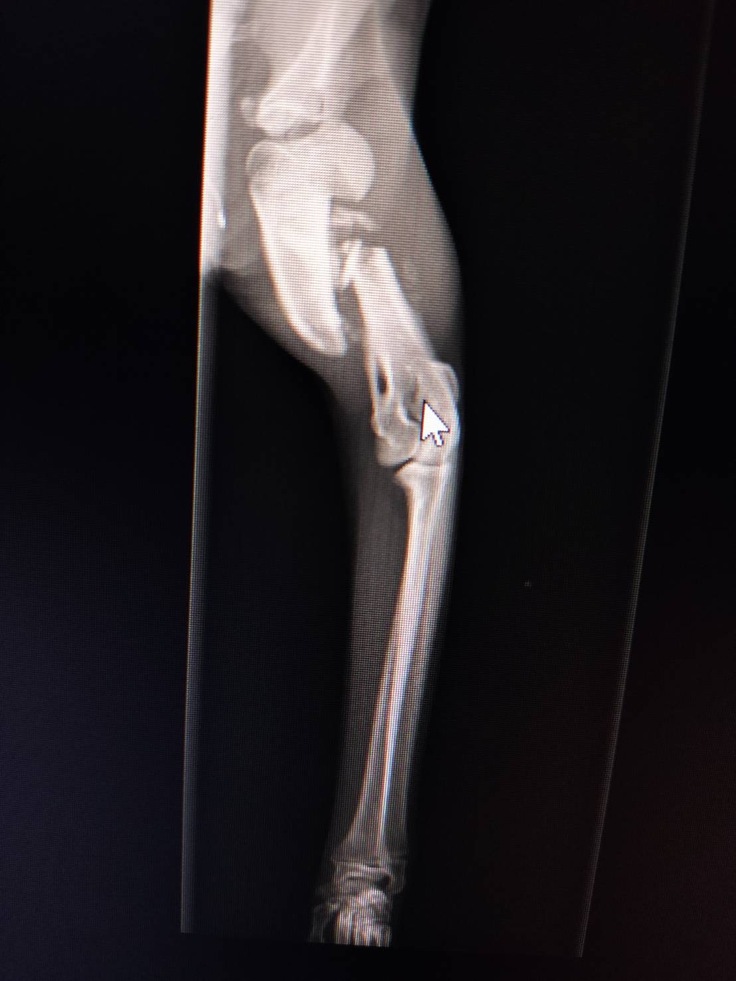

ボッキリ折れた大腿骨

すでに骨がずれたまま、くっつき始めてる